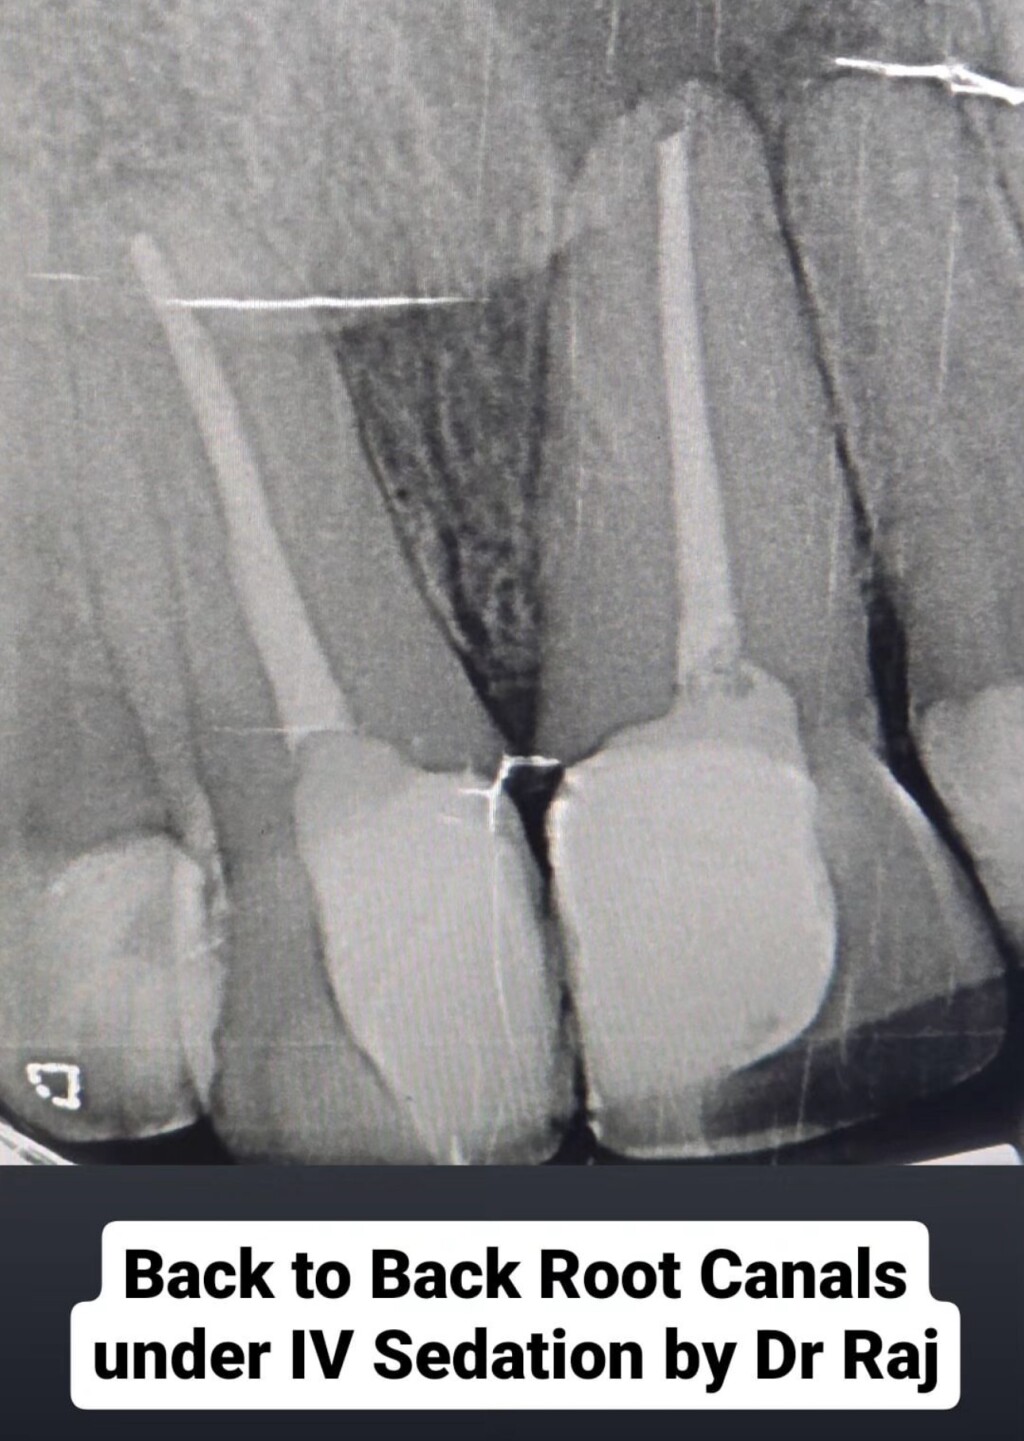

Today we completed extractions, fillings, gum treatment and even a root canal under sedation!